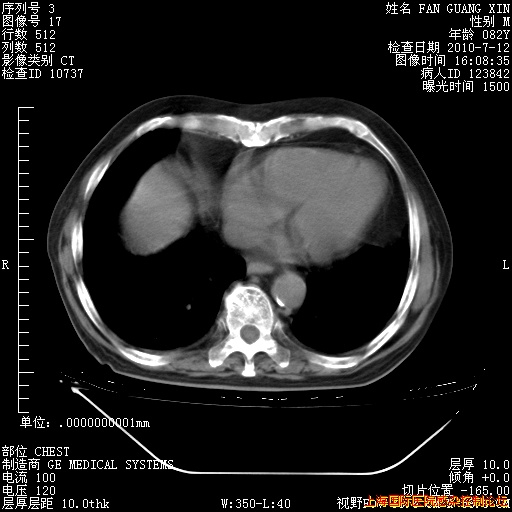

6月12日肺窗

6月12日纵膈窗

今天复查CT

今天CT

整整相隔30天的肺部CT好像有所好转啊。甲强龙减量第3天,需要观察体温。

海管,自昨日你和我通完话后,不知您岳父消化道症状有无缓解?体温怎样?阅读7.12日胸部ct,个人认为目前激素治疗是有效的,甲强龙减量是适宜的。因在抗痨治疗,需密切观察肝功、肾功能和血常规。不过,老年、长期住院和大量使用激素,很担心菌群失调发生